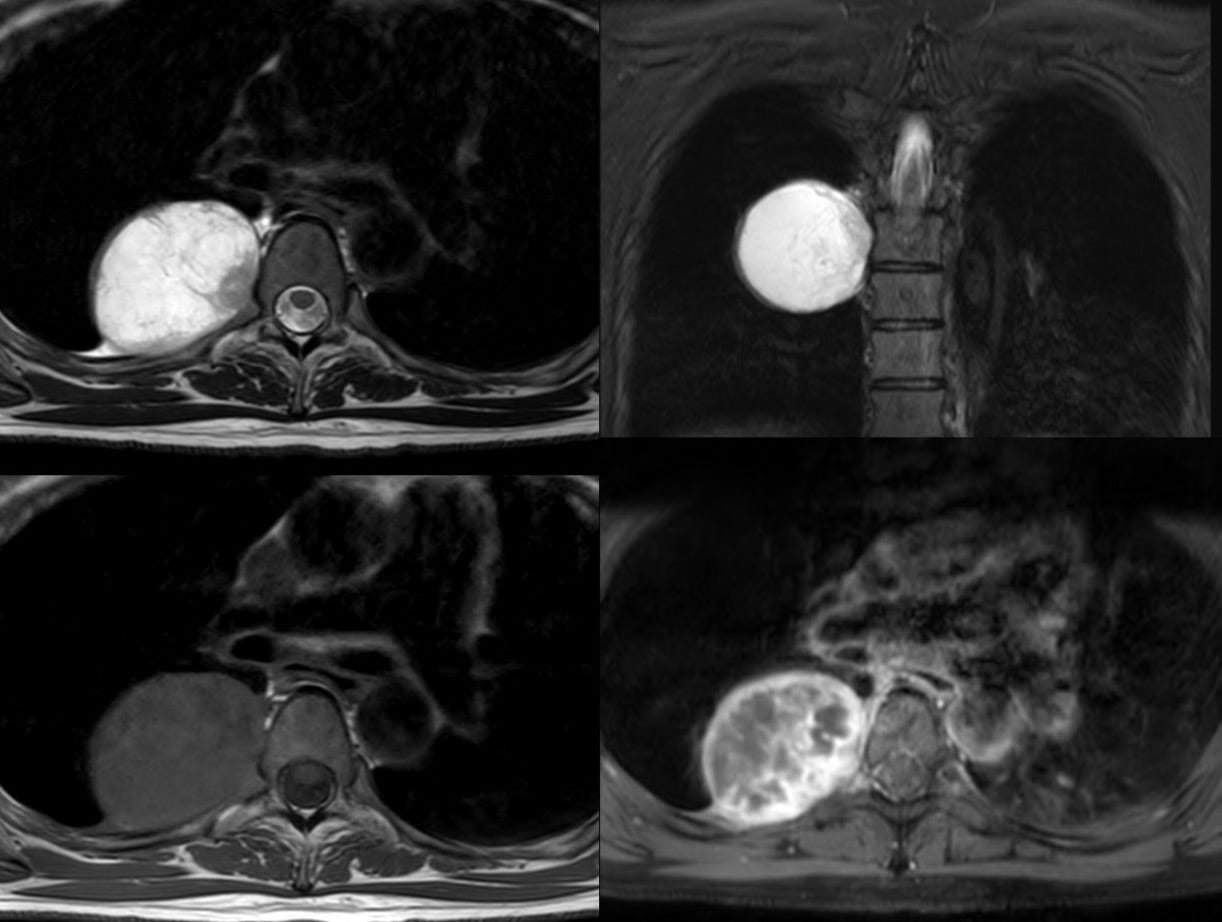

A 39-years old was found to have a mass in the chest on a CT chest done for COVID-19.

What is the likely diagnosis?

Paraganglioma

Schwannoma

Abscess

Hydatid cyst